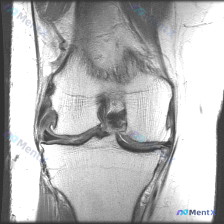

病例读片分享:膝关节MRI软骨异常的矛盾结果 刚整理了一份很有意思的读片病例,原提问说这张影像存在软骨异常,但我们完整分析完,结果和提问的判断矛盾,给大家分享一下整个过程。 影像基本信息 这是一张膝关节MRI冠状位影像,考虑是质子密度加权(PDWI)序列,这类序列分辨率高,非常适合观察膝关节的半月板...

刚整理了一个有意思的读片病例,临床和影像表现有点冲突,分享一下完整分析思路: 病例基础信息 这是一张膝关节MRI冠状位T1加权成像(T1WI),用户提示观察内容为「软骨异常」。 影像读片结果 先给大家说清楚各个结构的观察情况: 1. 骨骼结构:股骨远端、胫骨近端显示清晰,骨皮质低信号、骨髓腔中等信号...